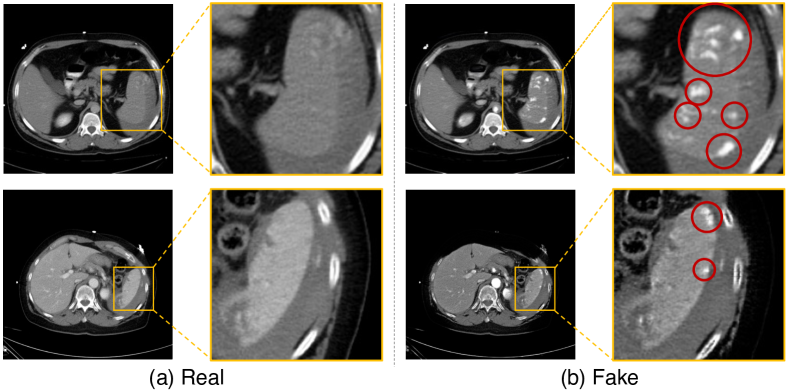

Refer to caption

Figure 1: Visual comparison of arterial and venous images (after alignment) as well as the manual segmentation of the splenic vascular injury. The injury volumes are different across phases.